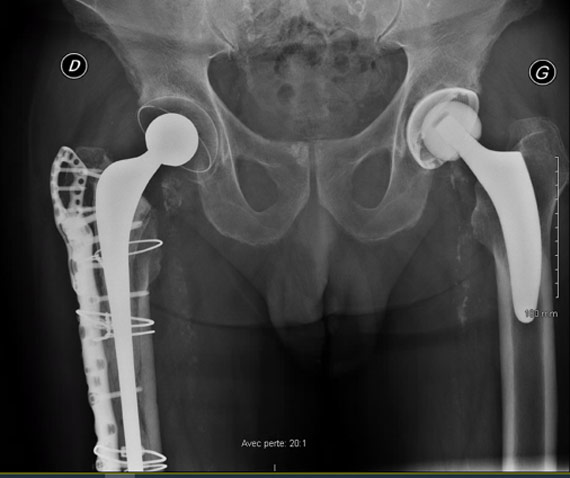

How would you manage this condition?

• ✔️Surgical stem revision and femoral ORIF with a plate

Final strategy decision

• In this case, we decided to perform a unipolar revision and ORIF with a plate (NCB Zimmer) and a cemented revision stem (Exeter Stryker), due to the extension of the fracture beyond the femoral isthmus.

• The patient was asked to avoid weight-bearing for 3 weeks.

• At 6 weeks post-op he was able to walk with one crouch